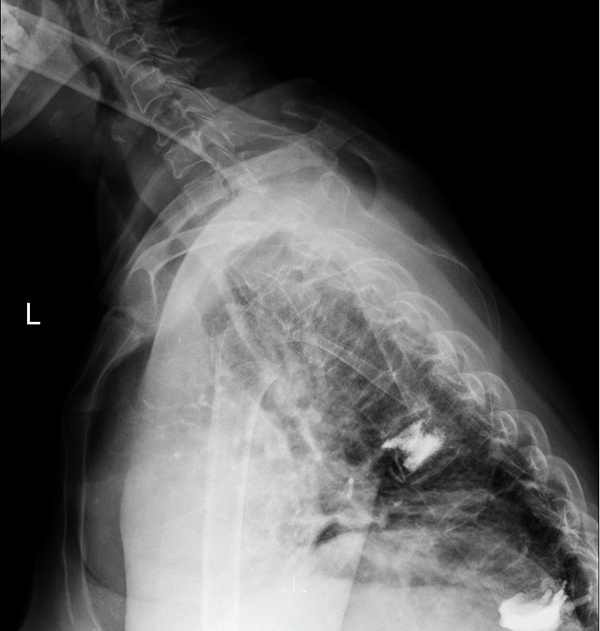

术前正位X片

术前侧位X片